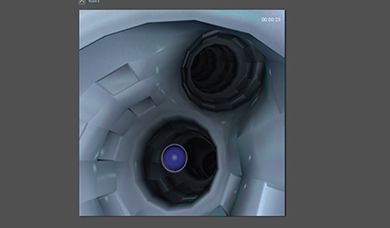

With the BRONCH Mentor simulator you can enjoy a flexible, all-inclusive, and highly reactive training environment.

It provides a comprehensive solution for flexible bronchoscopy training of pulmonary and critical care physicians, thoracic surgeons, anesthesiologists, interventional pulmonologists and others. Fundamental skill tasks and complete clinical procedures provide an optimal learning environment for motor, cognitive and coordinative skills acquisition, as well as diagnostic and therapeutic clinical hands-on experience towards competency.

- Realistic and comprehensive bronchoscopic simulation training away from patient, designed to support both team and solo training sessions